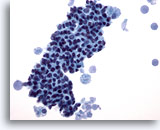

Figure 7

Breast FNA, Fibroadenoma.

This is another example of the branching appearance of ductal cells in fibroadenoma. 20x

Figure 7

Breast FNA, Fibroadenoma.

This is another example of the branching appearance of ductal cells in fibroadenoma.

20x